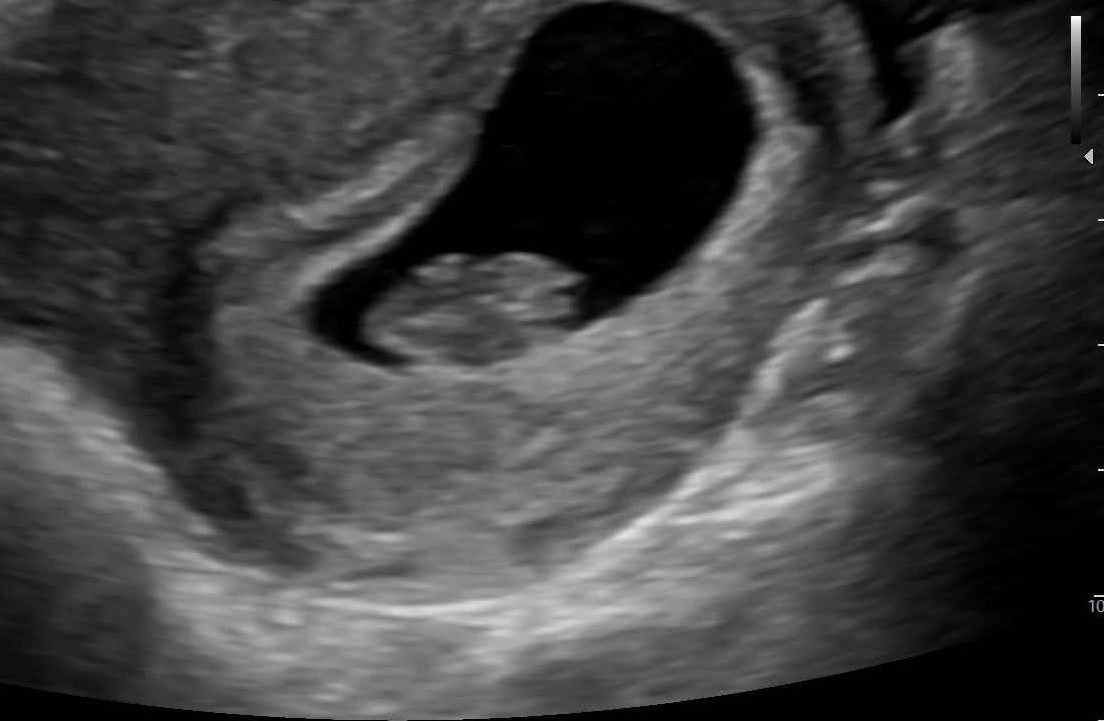

Just wanted to share two different ultrasound results in case it helps any of you. The doctor we saw for the first ultrasound came in right after and basically said we had a "slow" heartrate and could expect miscarriage. My research and instincts told me that was incorrect, and I pushed back. I had a blighted ovum last year, which was basically an empty sac at the same time (6 wks, 2 days) so seeing fetal pole and heartbeat seemed great to me! I was honestly shocked at the doctor's reaction.

The second doctor (we saw her today after the second ultrasound) told me it was irresponsible for them to flag anything over 100 at 6 weeks and that my first measurements were fine. It goes to show that there is variation among medical professionals, as well as different approaches, and on the earlier side, assuming certain elements are in place, it's ok to be optimistic!

For reference here are the previous ultrasound notes / measurements: Ultrasound date: 12/19/22 Gestational Age: 6 wks, 3 days Elements Present: Yolk sac, fetal pole, heartbeat CRL (crown rump length): .67 cm Heart Rate = 107 Due date = 8/10/23